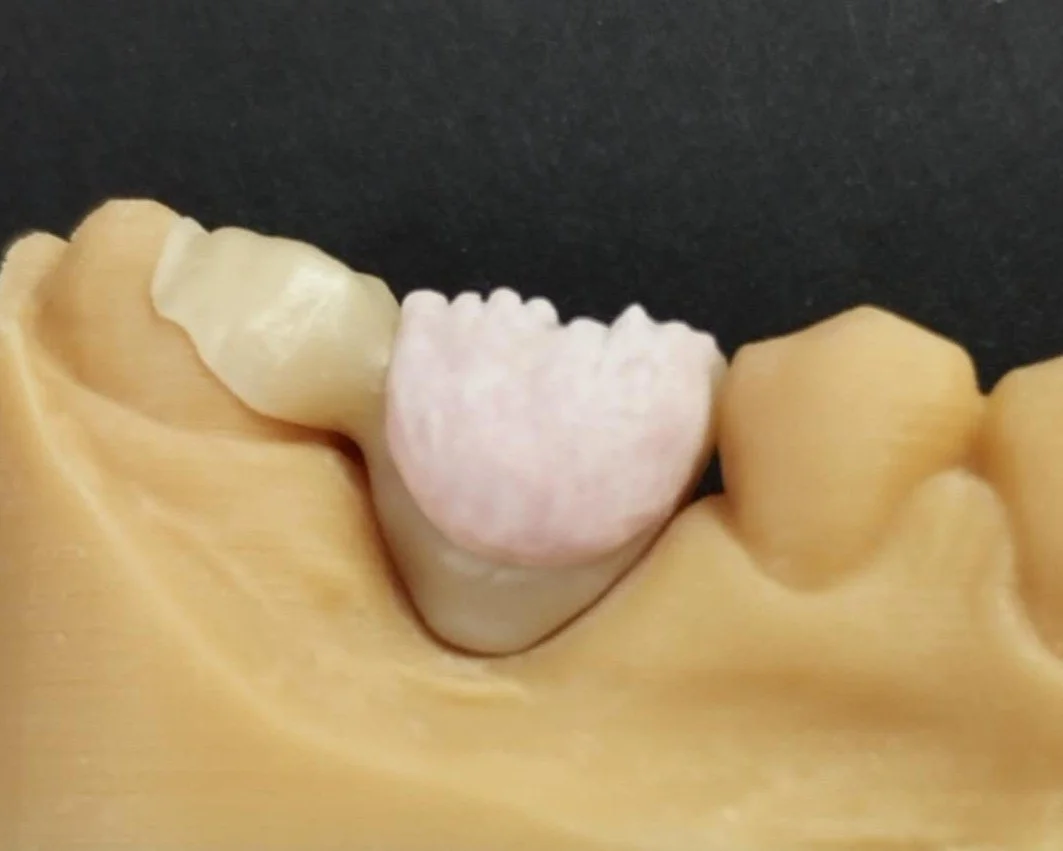

Relativement récents, les bridges collés cantilever postérieurs constituent une alternative fixe, fiable et véritablement minimalement invasive aux implants dans les secteurs postérieurs. Cette thérapeutique qui repose sur des indications bien précises est parfois débattue avec passion sur les réseaux sociaux ou dans les congrès scientifiques. Cependant des études cliniques existent, tout comme des recommandations validées dans des journaux internationaux. Leur succès repose sur des préparations et des principes biomécaniques rigoureux, pourtant simples à intégrer au quotidien. Cette intervention propose un guide clair et opérationnel incluant indications, étapes clés, protocoles d’adhésion et réglages occlusaux pour les mettre en œuvre avec confiance et reproductibilité.